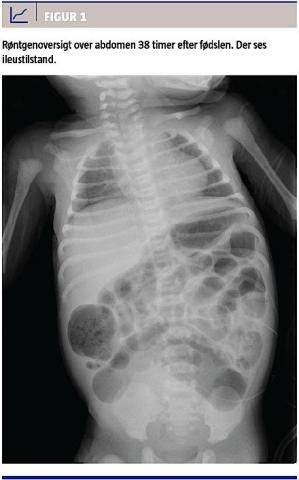

På grund af manglende mekoniumafgang blev der 38 timer efter fødslen foretaget en røntgenoversigt over abdomen, hvorved man fandt en ilieustilstand (Figur 1). Ved laparotomi fandt man dilateret tarm ned til den peritoneale omslagsfold ved rectosigmoideum, hvorfor man på mistanke om mb. Hirschsprung anlagde en descendendostomi med blindlukning af rectum. Diagnosen blev senere bekræftet ved en biopsi fra rectum. Postoperativt fik barnet adominalt kompartmentsyndrom og måtte reopereres med resektion af et 3 cm langt stykke iskæmisk tyndtarm. Herefter var der er et ukompliceret forløb.